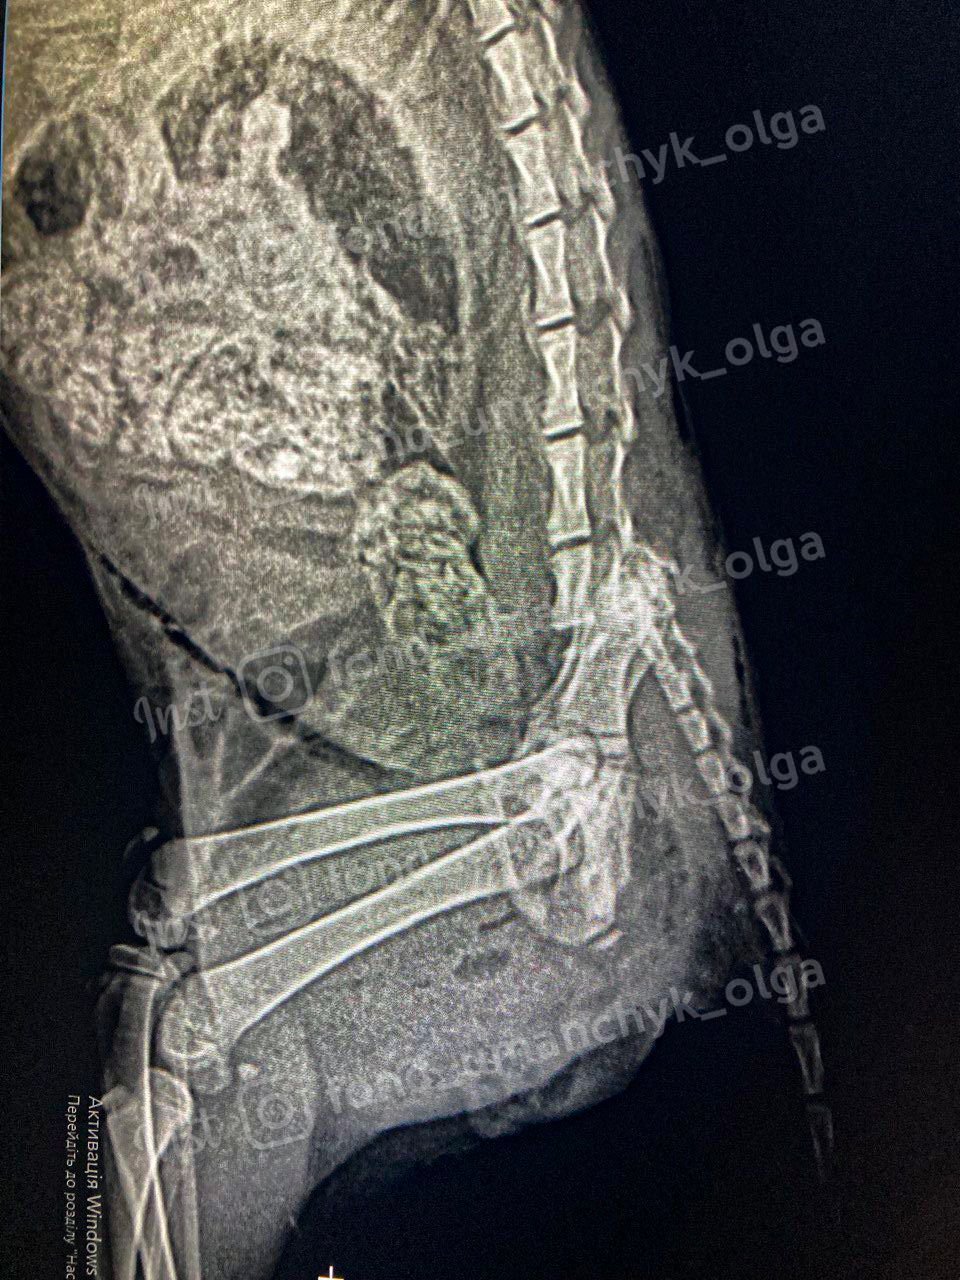

"За першим припущенням було схоже, що малюка порвали собаки, але характер ран і травм, виявлених у клініці, каже, що маленького побили. Він міг потрапити в двигун машини або просто до рук садиста. Попередній діагноз: травма хребта, перебитий таз і хвіст, розрив кішківник, септичний шок, перелом суглобів обох задніх лапок, множинні рани по всьому тілу, рідина в черевній порожнині. Ми можемо втратити кошеня", - написала Ольга.